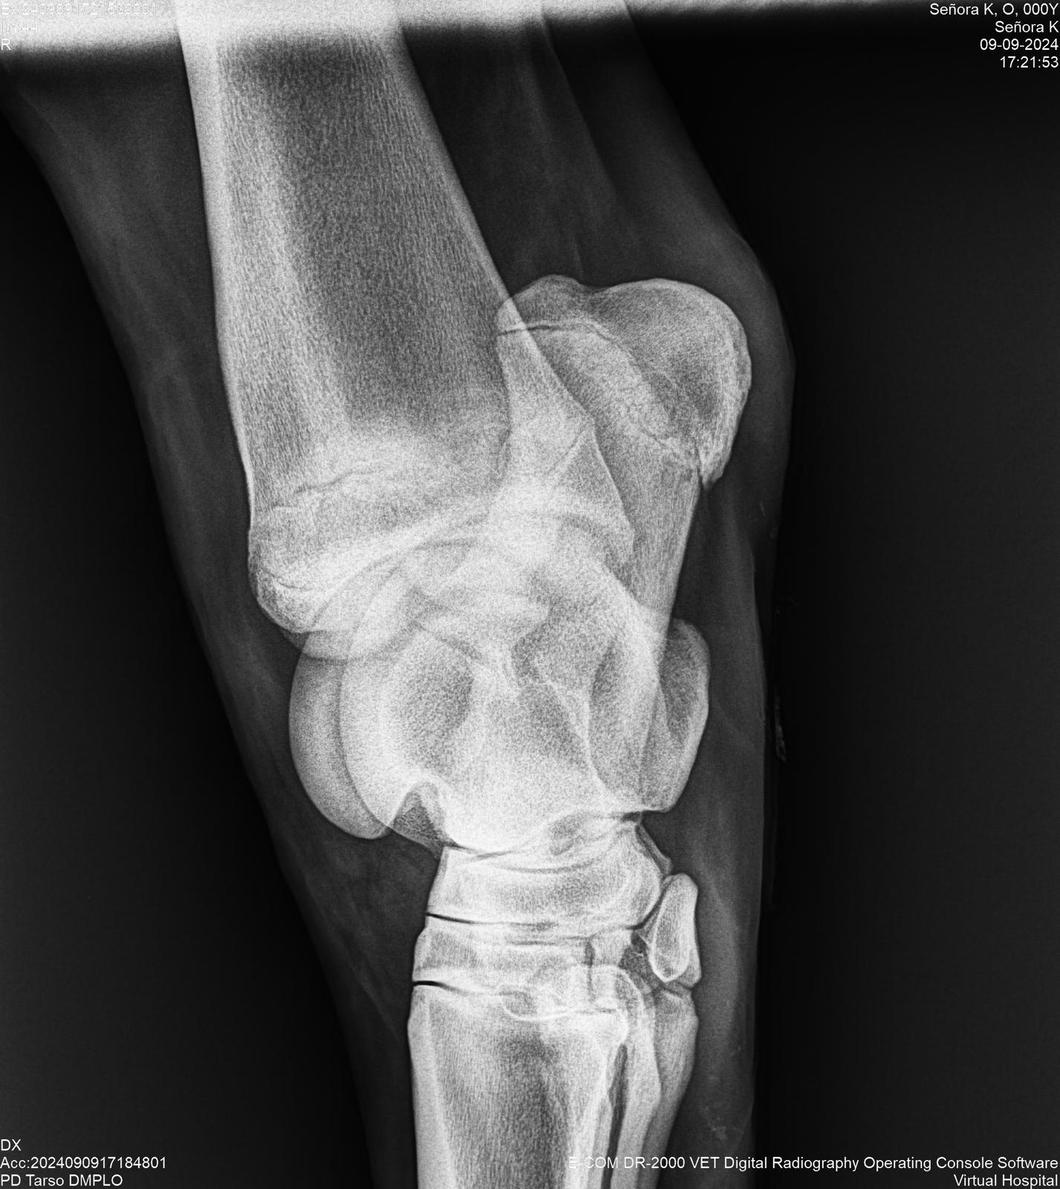

LOTE 44, SEÑORA K

Identificador: #291147-

Generacion 2022